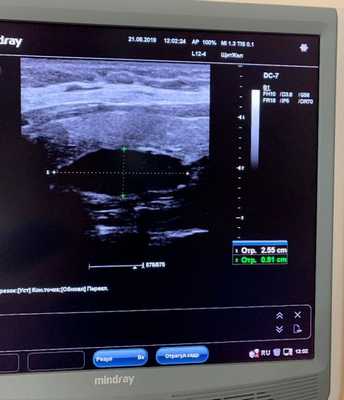

- УЗИ околощитовидной железы — выявило аденому правой нижней околощитовидной железы размером 1,7 см;

Исследуемая область при УЗИ сверху ограничена бифуркацией (разделением) сонной артерии, снизу — грудинной вырезкой, сбоку — сонной артерией/внутренней ярёмной веной [7] . Паращитовидные железы нормального размера обычно не визуализируются с помощью ультразвука. Аденомы проявляются в виде овальных анэхогенных (выглядят чёрными) или гипоэхогенных (выглядят тёмно-серыми) образований, расположенных кзади от щитовидной железы. Обычно можно увидеть эхогенную (светлую) линию, которая отличает щитовидную железу от увеличенной паращитовидной железы. Более крупные аденомы чаще имеют кистозные изменения.